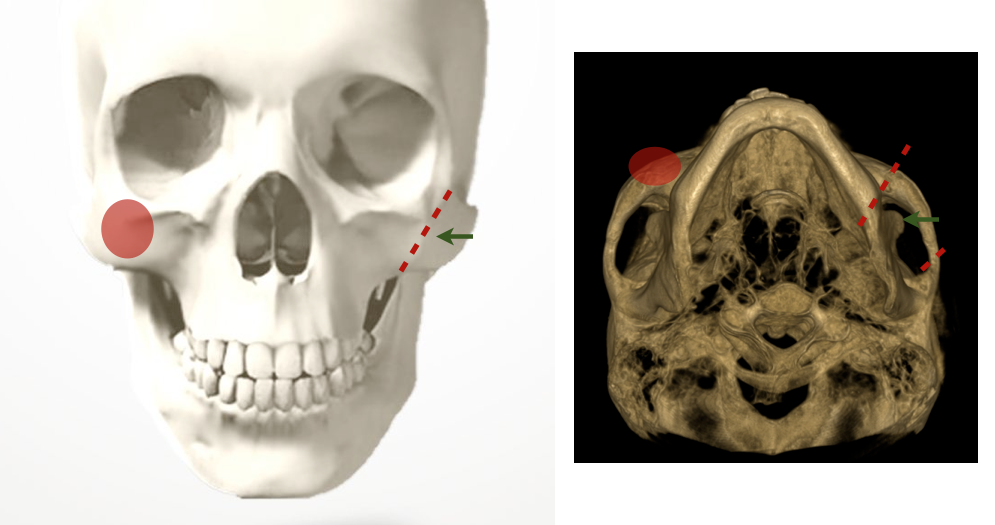

顴骨 (zygoma) 是決定中臉寬度及立體感的骨骼,顴骨弓 (zygomatic arch ) 決定了臉的寬度而顴骨體 (zygomatic body) 則決定了臉頰隆起 (malar eminence) 的幅度。西方人由於眼眶骨立體,較明顯的顴骨使得眼睛看起來更深邃,東方人眼眶較平,配上較寬或較高的顴骨反而突兀,甚至有點感覺不易親近。

A: 顴骨弓    B: 顴骨體

手術方式一般也分成兩個部份,顴骨弓過寬的處理方式是將顴骨弓兩端截斷再內移,才能達到較好的效果,而顴骨體過高則可用磨骨的方式處理。